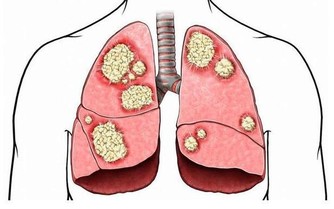

(4)高血脂會導致肝部功能損傷

長期高血脂會導致脂肪肝,而肝動脈粥樣硬化後受到損害、肝小葉損傷後,結構發生變化,而後導致肝硬化,損害肝功能。